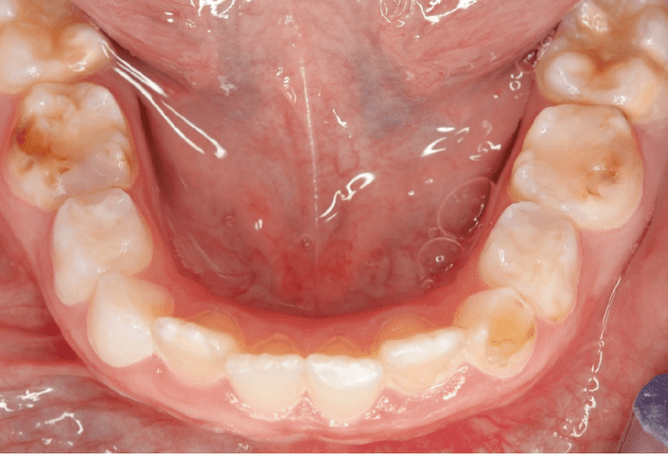

Pictures above: Hypomineralisation seen on the primary second molar, the secondary (adult) first molar and some on the primary canine. Hypomineralisation seen on the adult incisor tooth.

Hypomineralisation or 'chalky molars' is one example of a developmental dental defect (D3) and is the most common of the enamel defects effecting 1 in 5 children. It causes a lot of suffering around the world. It typically effects the 6-year old molar, but other molars effected can be the 2-year old molar and in some cases even the adult front teeth can be effected.

Hypomineralised teeth are often soft and porous and can often crumble away with brushing and eating. This causes the dentine (which is 'alive') to be exposed and react to hot/cold things, eating and brushing causing pain.